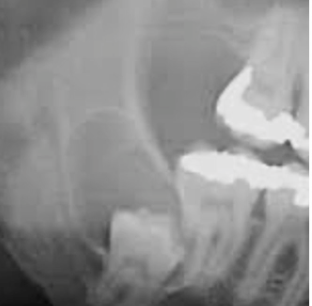

what is this?

the maxillary sinus

lies above the premolar/molars